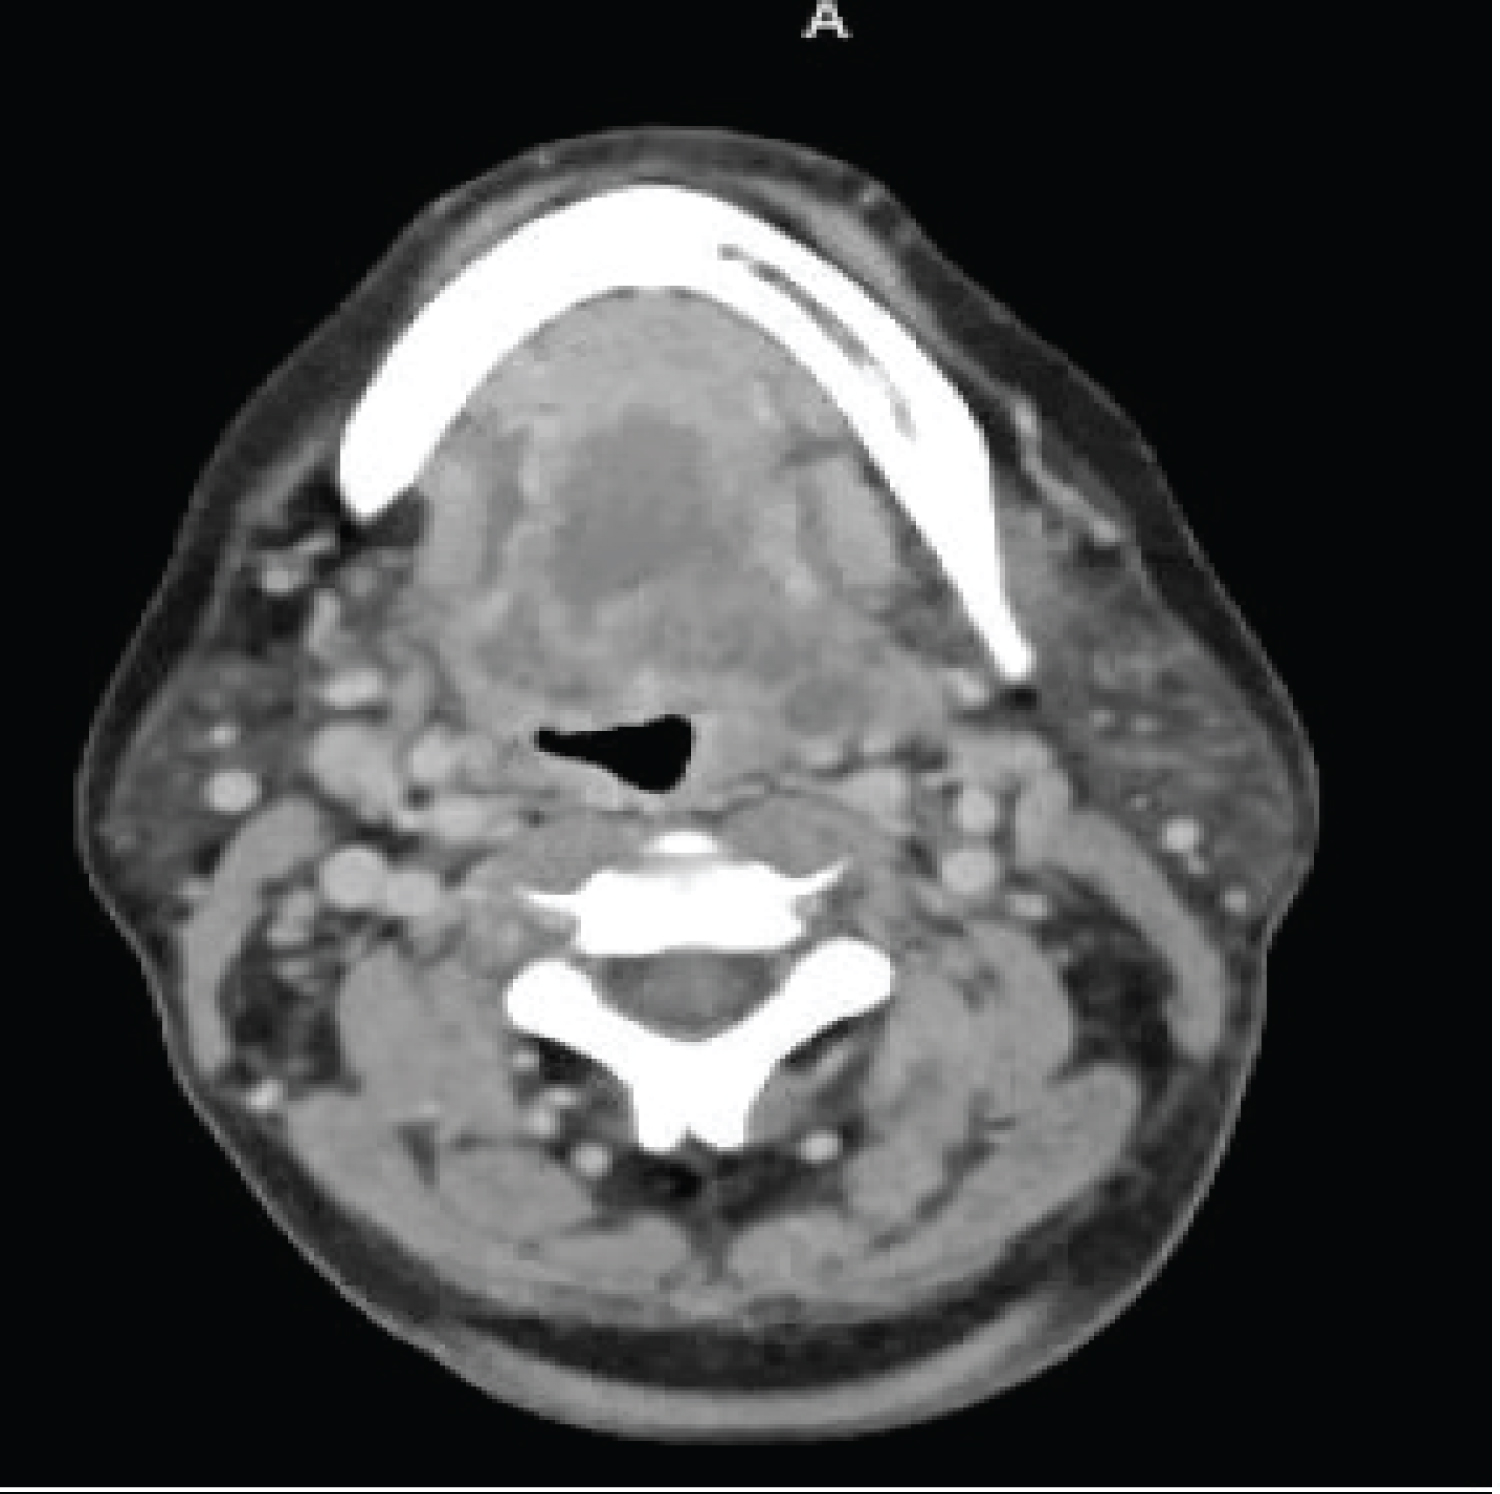

FB is a 57-year-old female with multiple comorbid medical conditions including tracheal stenosis status-post multiple dilations, coronary artery disease, hypertension, and end-stage renal disease (ESRD) receiving hemodialysis who presented with a 4-day history of bilateral odynophagia with associated right-sided neck swelling and new onset fever, sore throat, shortness of breath, and bilateral neck swelling. The patient also reported associated chills, nonproductive cough, nausea, and one episode of nonbilious, non-bloody emesis. She was able to tolerate oral intake at this time and presented without drooling or other signs of impending airway obstruction. The patient was febrile at presentation with a temperature of 38.7 °C. CT was obtained which demonstrated a multiloculated fluid collection within the floor of the mouth suspicious for an abscess and significant tracheal stenosis at the level of the thyroid gland measuring 8 × 6 mm. The collection of fluid at the base of the tongue had its largest pocket measure 2.2 × 1.4 cm (Figure 1). Blood cultures were obtained at the time of her presentation, and she began receiving empiric intravenous (IV) vancomycin and metronidazole. IV dexamethasone 10 mg q6 hours was also administered at this time. The patient was subsequently admitted to the medical intensive care unit for airway monitoring and continuous pulse oximetry. Blood cultures revealed Staphylococcus epidermidis on hospital day 3 and her antibiotic regimen was changed to IV vancomycin and ampicillin-sulbactam per our infectious disease team recommendations. She was deemed stable by our otolaryngology team to be transferred to the hospital floor on hospital day 4, however, the patient began reporting increased stridor, dysphonia, pain, and neck swelling on hospital day 5. Repeat CT demonstrated an increase in the fluid collection in the right floor of the mouth which now measured 3.5 × 2 cm (Figure 2). The patient was a febrile at this time, but was being closely monitored for acute decompensation. Surgical planning for incision and drainage of the growing floor of mouth abscess was made and the patient was boarded for surgery. A direct laryngoscopy was performed to visualize and drain the left low oropharyngeal/glossotonsillar sulcus and infected cystic lesion. A large amount of purulence was drained and sent for culture. She also was found to have a small to medium sized vallecular cyst which was biopsied and sent for pathology with no associated purulence. She tolerated the procedure well and seemed to be improving clinically with reduced neck swelling and improved dysphagia. Her steroids were slowly tapered post-procedure. Surgical pathology of the biopsied vallecular cyst resulted in benign squamous mucosa with a lymphocytic infiltrate. Final bacterial cultures from the oropharyngeal abscess grew Enterobacter cloacae resistant to ertapenem, few Candida tropicalis , few Streptococcus viridans , and rare Lactobacillus species. Her antibiotic regimen was subsequently switched to oral meropenem 500 mg q 24h for Enterobacter coverage and oral fluconazole 200 mg QD for candida coverage. She was subsequently discharged home on oral fluconazole, sulfamethoxazole/trimethoprim, and metronidazole with home health care. She will continue to follow-up with ENT for her subglottic stenosis.

Figure 1: The collection of fluid at the base of the tongue had its largest pocket measure 2.2 × 1.4 cm.

View Figure 1

Figure 1: The collection of fluid at the base of the tongue had its largest pocket measure 2.2 × 1.4 cm.

View Figure 1